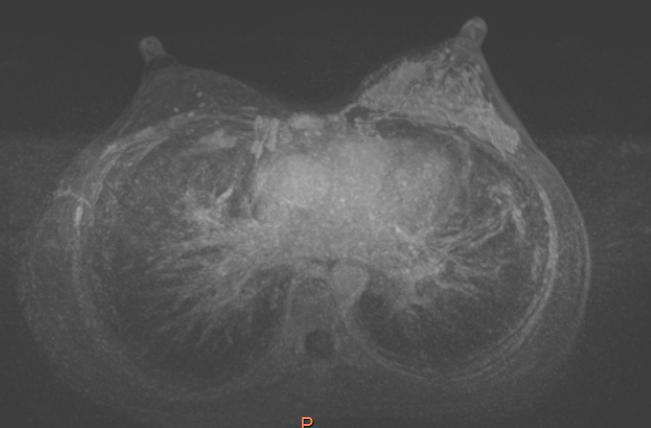

• 乳腺 MRI:1.左乳多发肿块,多发区域强化,5 cm x 2 cm x 3 cm,考虑乳腺癌(多中心),BI-RADS:5 类;2.左腋窝多个肿大淋巴结,3 cm x 1.8 cm,考虑转移;3.胸骨、右侧肋骨骨质破坏,结合骨扫描。

图片

图 3 乳腺 MRI